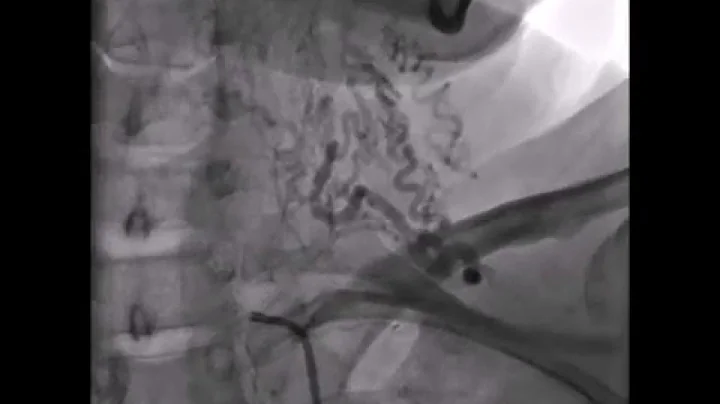

Dr. Ramzan Zakir, Subclavian And Brachiocephalic Stenting: Indications And Techniques